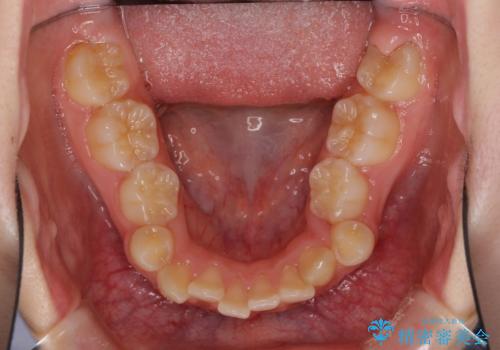

乳歯が3歯残っており、下顎は左右ともに後続永久歯がない状態でした。

口元が突出しており、口が閉じにくかったため、乳歯を含め上下5歯を抜歯して矯正治療を行うこととしました。

下顎の乳歯は永久歯と比べて幅が大きいため、抜歯した場合のスペースが大きく、治療には長期間を要することが一般的です。

今回の患者様は中学生ということもあり、成人の患者様と比べ動きが速く、2年間で治療を終えることができました。